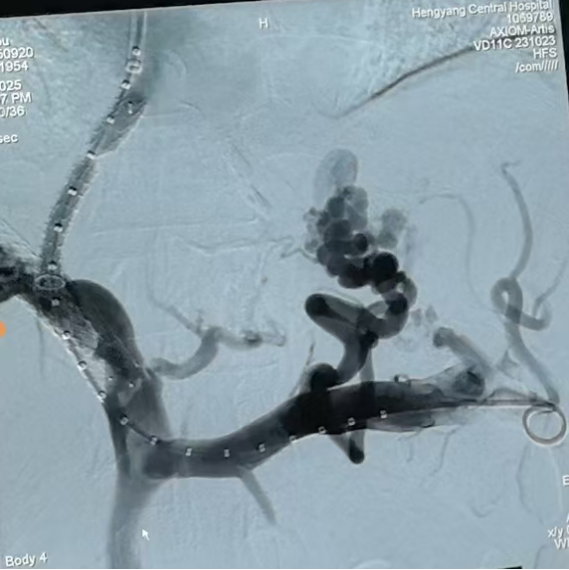

圖一:TIPS術(shù)中

第三步,手術(shù)實施與術(shù)后管理9月20日,在消化介入團(tuán)隊精湛操作下,成功為患者實施TIPS支架修補術(shù)。術(shù)中,團(tuán)隊克服了患者肝內(nèi)血管結(jié)構(gòu)因既往手術(shù)和肝硬化而異常復(fù)雜等諸多困難,精準(zhǔn)地在門靜脈與肝靜脈之間建立了有效分流,并置入覆膜支架以確保分流道長期通暢。術(shù)后門靜脈壓力即刻顯著下降,達(dá)到了預(yù)期血流動力學(xué)目標(biāo)。

圖二:TIPS術(shù)中影像